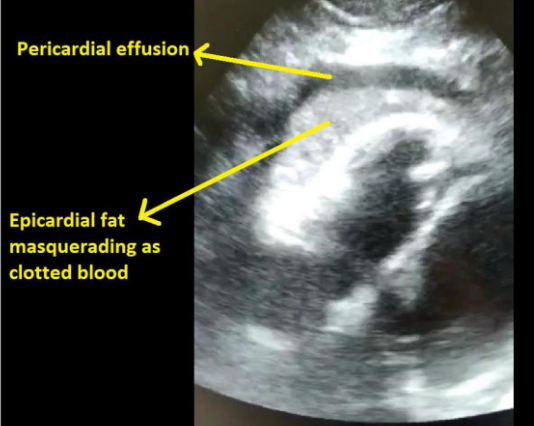

Bedside ECHO showed an echogenic lesion around the right ventricle with a surrounding rim of pericardial fluid. In the context of recent STEMI and PCI, concerns were raised if this was hemopericardium secondary to myocardial rupture or coronary vessel injury from the recent procedure.

Subcostal view of the heart showing the epicardial fat and pericardial effusion

Epicardial fat is a common finding. Its thickness is a marker of cardiovascular risk and has been associated with insulin resistance, atherosclerosis, metabolic syndrome, and coronary artery disease. It can be confused with hemopericardium or pericardial effusion. Features suggestive of epicardial fat are that it is usually found around the ventricles and is less likely to be seen around the atria or be circumferential around the heart. Epicardial fat is adherent to the outer wall of the myocardium and moves with it during cardiac cycle. It is not associated with tamponade physiology or dilated inferior vena cava. In this case the associated small rim of pericardial effusion was thought to be secondary to the recent MI.